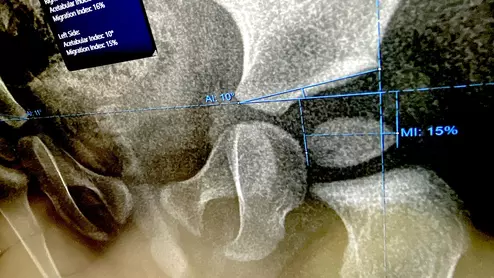

Many new imaging solutions were on display at the world's largest health informatics conference, held at McCormick Place in Chicago.

Innovation at work